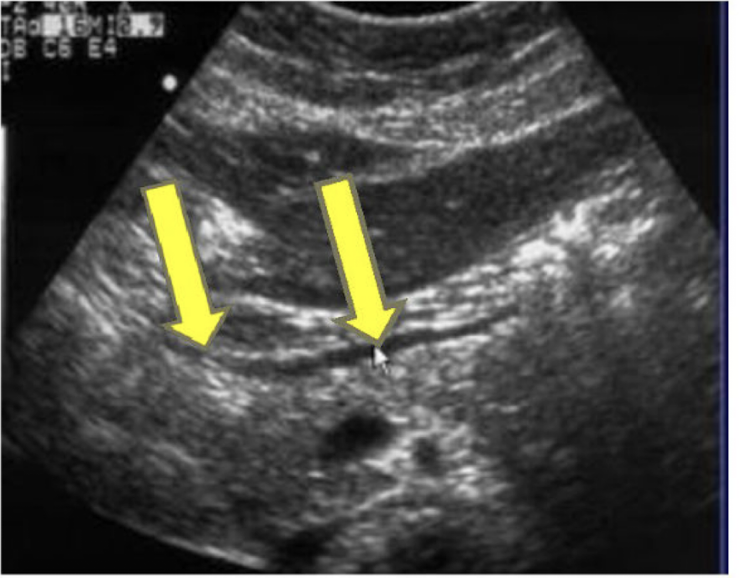

What are the yellow arrows pointing to?

Posterior wall of stomach (BE CAREFUL not to confuse with MPD)